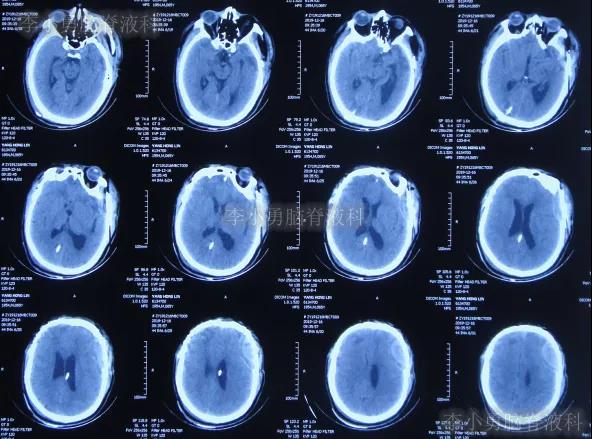

2019年10月20日患者骑电动车在马路上行驶时被大货车撞倒,当时意识清楚,只感到有些头晕,未在意就自行回家,但回家后约3-4小时出现头晕加重,并伴有恶心呕吐的症状,家人急送到当地的河北省邯郸市某医院,查头颅CT示脑出血(图-1);既往病史2015年曾因头部外伤致硬膜下血肿,进行了钻孔引流术。

图-1:2019年10月20日头颅CT

急诊进行了开颅去骨瓣血肿清除术,术后次日查头颅CT示去骨瓣术后(图-2)。

图-2:2019年10月21日头颅CT